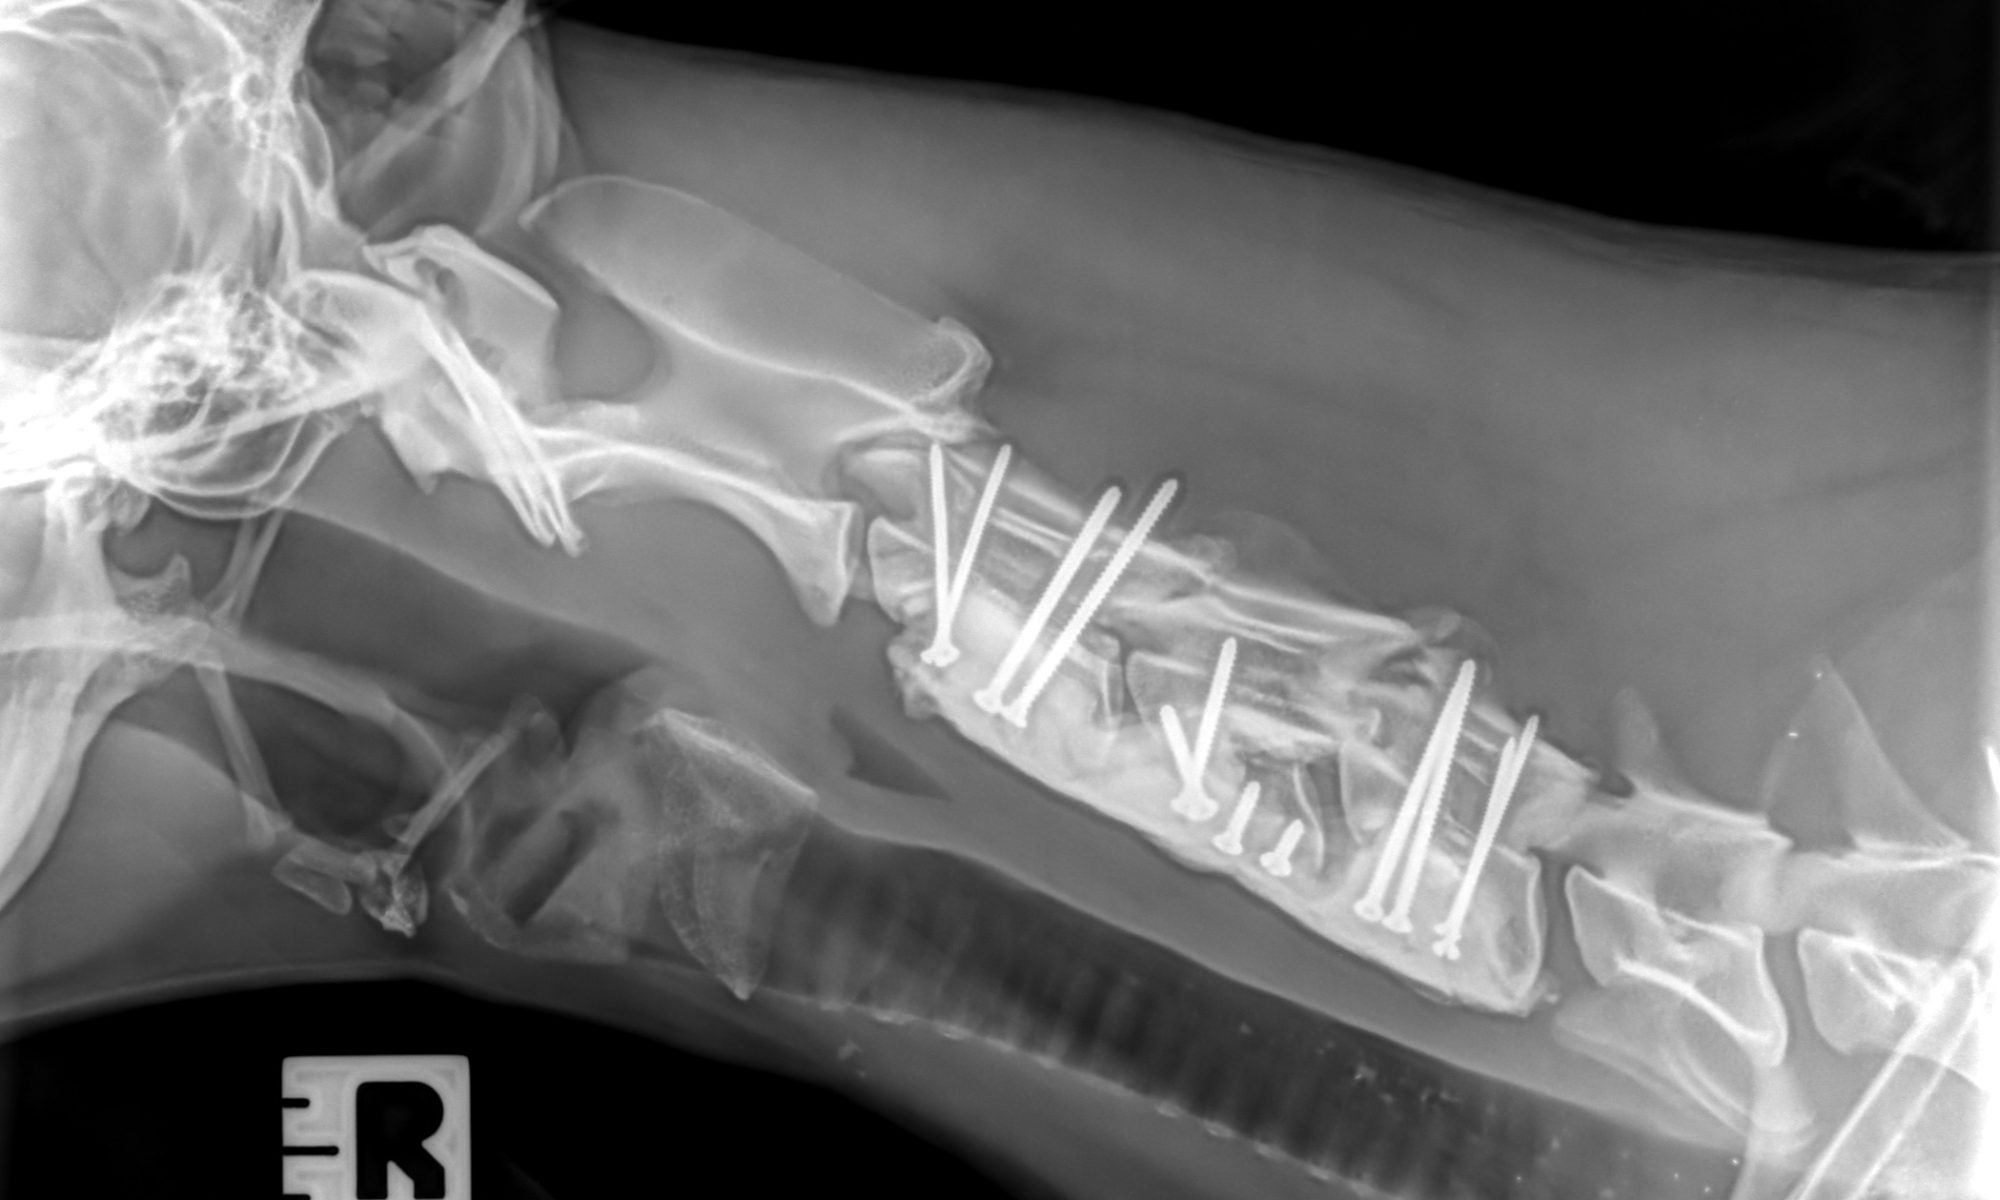

A Lancashire dog owner has described her shock and dismay at seeing her tiny dachshund puppy left yelping in agony after suffering a broken leg in a freak accident. The injury happened as Janina Brocklesby, from Lytham St Annes, was walking little four-month-old Rizzo with her other dog, a 14-year-old Doberman-Black Labrador crossbreed called Freeman.…